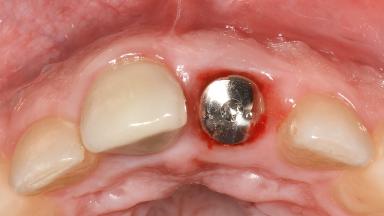

A 37-year-old male patient was referred to the Department of Periodontology at the University of Bern, Switzerland, by a private dentist. Tooth 21 had been lost due to trauma and had been replaced with an implant and a cemented single crown. The tapered-effect tissue-level implant had a diameter of 4.1 mm, a length of 12 mm, and a sandblasted and acid-etched (SLA) surface (Straumann Dental lmplant System; Institut Straumann AG, Basel, Switzerland). The metal-ceramic crown had been cemented permanently, leaving a submucosal gap between the implant shoulder and the crown margin. Absence of marginal bone loss apical to the polished transmucosal neck of the implant could be observed .